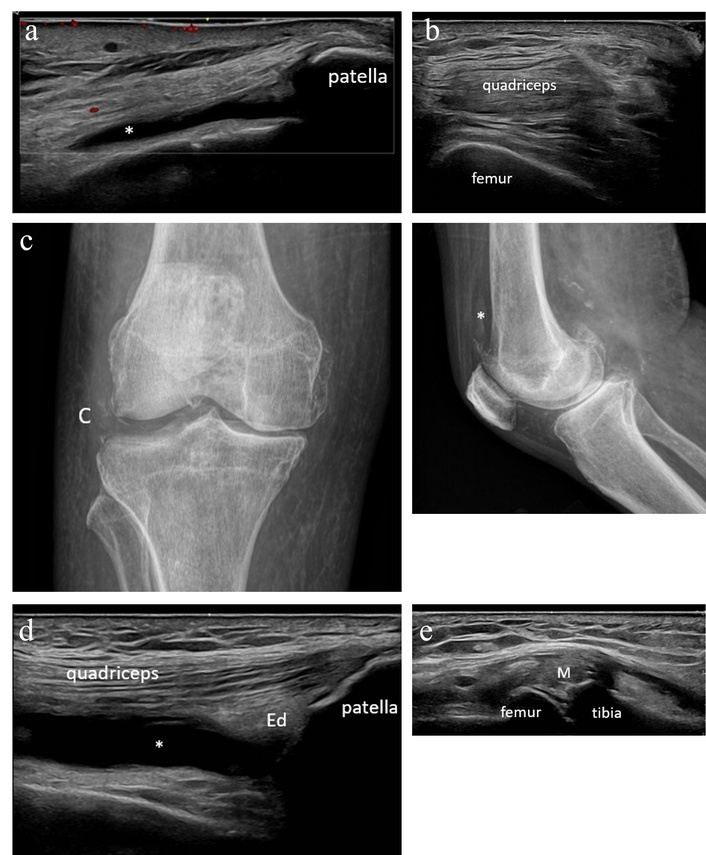

Patient 4 is a 79-year-old male with a history of melanoma treated with nivolumab, who presented to rheumatology describing worsening bilateral knee pain that began following his first immunotherapy infusion (dual therapy with nivolumab and relatlimab). On exam, he was found to have limited bilateral knee range of motion with mild swelling and small effusions; his exam was otherwise unremarkable. Inflammatory markers had been recently elevated (sedimentation rate 36 mm/h and C-reactive protein 52 mg/L). MSKUS was performed without evidence of synovitis (Figure 4a–b). Both knees were aspirated and injected under ultrasound guidance with a non-inflammatory cell count. A radiograph of the right knee demonstrated moderate medial and patellofemoral compartment osteoarthritis and chondrocalcinosis (Figure 4c).

Case 4 ultrasound images. (a) Left knee suprapatellar longitudinal ultrasound with no synovial hypertrophy but a small effusion (*) present in the lateral aspect of the suprapatellar recess. (b) Right knee suprapatellar transverse ultrasound with no synovial hypertrophy or effusion. (c) Radiographs of the right knee demonstrate a small effusion (*), moderate medial and patellofemoral compartment degenerative change, and chondrocalcinosis (C). (d) Right knee suprapatellar longitudinal ultrasound with suprapatellar fat pad edema (Ed) and moderate effusion (*). (e) Right knee medial longitudinal ultrasound with meniscal protrusion (M), osteophytosis, and a few deposits of chondrocalcinosis in fibrocartilage.

Thereafter, the patient had persistent relief in his left knee but recurrence of right knee pain, leading him to again present to the clinic 3 months later. At that time, MSKUS was repeated with demonstration of right knee synovial hypertrophy and hyperemia (Figure 4d–e). The right knee was aspirated and injected with synovial fluid, demonstrating a non-inflammatory cell count but intracellular calcium pyrophosphate crystals. He was diagnosed with pseudogout and started on scheduled colchicine for prophylaxis with benefit.

This case again highlights the ability of MSKUS to detect the presence of inflammatory arthritis even in the setting of a nondiagnostic physical exam and noninflammatory synovial fluid. Without MSKUS, the treating rheumatologist may have easily attributed this patient’s symptoms to activated osteoarthritis and deemed the calcium pyrophosphate crystals as likely consistent with asymptomatic chondrocalcinosis in the presence of noninflammatory synovial fluid.